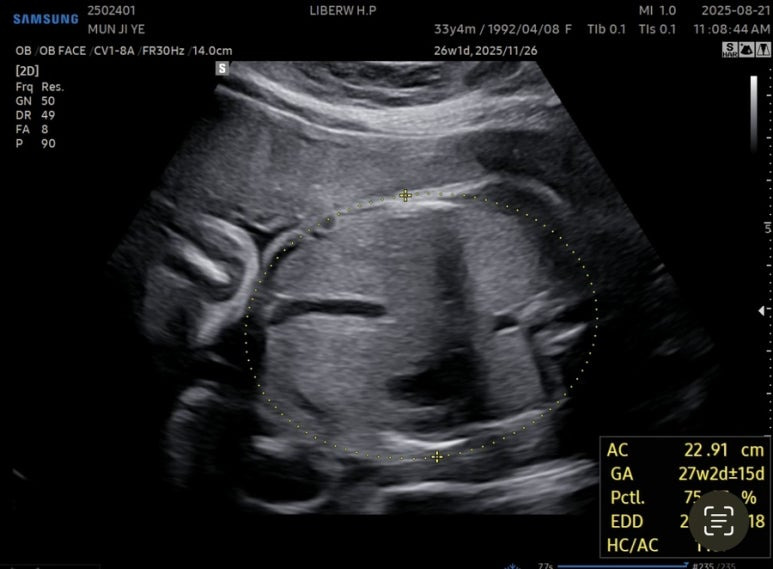

27주차 사탕이는

머리둘레 6.62cm

배 둘레 22.91cm

다리길이 4.61cm

몸무게 956g

심장박동수 150bpm

경부길이 3.44cm

양수량도 적당했다